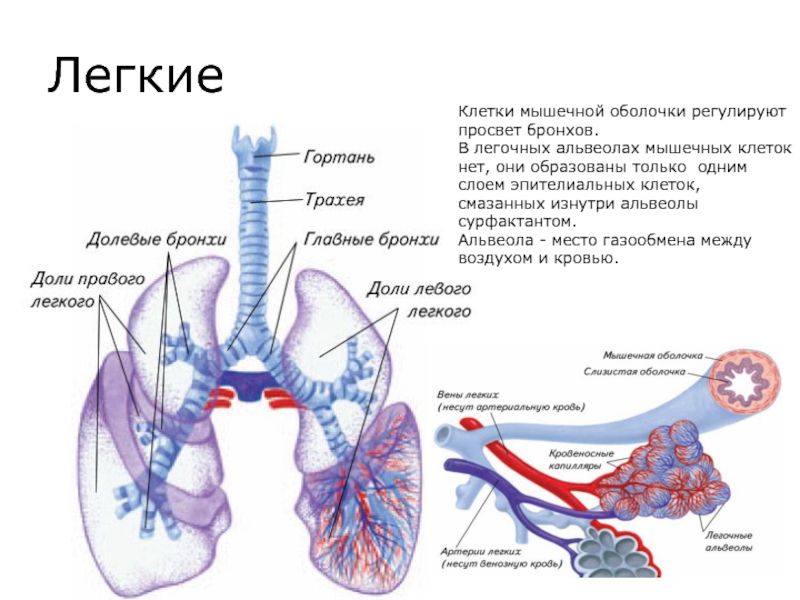

Изменения в легких при коронавирусе

Инфицирование новым штаммом вируса SARS-CoV-2 вызывает в органах дыхания острый воспалительный процесс.

Изначально вирус поражает верхние дыхательные пути, а затем может проникать в

легкие и провоцировать развитие вирусной пневмонии. Она в свою очередь может

осложняться присоединением вторичной бактериальной инфекции, что приведет к

вирусно-бактериальному воспалению легких, которое лечится уже серьезнее, дольше

и хуже переносится организмом.

При коронавирусной инфекции больше всего страдают альвеолы,

являющиеся мельчайшими легочными структурами. Они имеют форму пузырьков и

отвечают за осуществление газообменных процессов, т. е. поглощение кровью

кислорода и ее очищение от углекислого газа. Коронавирус разрушает стенки

альвеол, что приводит к нарушению этих процессов, а также накоплению в альвеолах

воспалительного экссудата.

Это может приводить к замене пораженных участков плотной

соединительной тканью, не способной к растяжению, что и называют фиброзом

легких. В таких ситуациях они не смогут полноценно выполнять дыхательную

функцию, а их жизненный объем уменьшится, что при обширном замещении нормальной

ткани легких даже может стать причиной инвалидности.

Возникающая в результате нарушения газообмена гипоксия, т.

е. кислородное голодание, отрицательно сказывается на работе всего организма,

поскольку все органы страдают от нехватки кислорода. На КТ или рентгеновских

снимках в таких ситуациях становятся заметными белые пятна, что еще называют

эффектом матового стекла. Впоследствии при развитии фиброза на снимках могут

визуализироваться особые затемнения, указывающие на пневмофиброз. Хотя подобные

изменения характерны не только для коронавирусной инфекции, но и для других

тяжелых бактериальных и вирусных пневмоний.